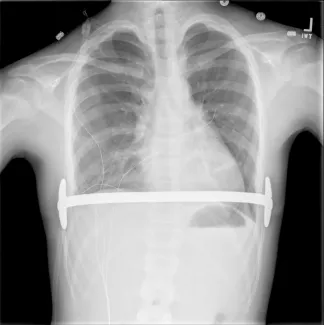

Preoperatively, your insurance carrier may require a CT scan to measure the Pectus Severity Index (PSI, also known as the Haller Index), which is the the ratio of the width of the chest wall to the depth at the deepest point of the deformity. This value usually must exceed 3.2 to be considered severe enough to be surgically corrected.

Repair with a metal pectus bar, called the Nuss Procedure, is achieved by bending a stainless bar to fit the chest wall. The bar is then inserted and secured through a small incision under each arm using the aid of a endoscope to monitor and avoid injury to the heart during insertion. The bar goes over the ribs and under the sternum, to push the sternum forward into the new position. The ends of the bar are secured to the chest wall. This procedure takes between 1–2 hours.